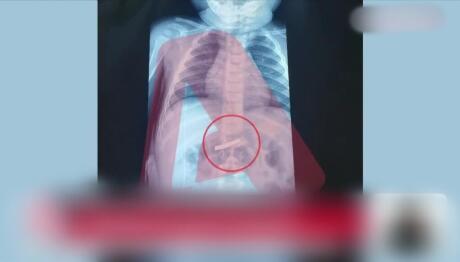

Ξαφνική αδιαθεσία για τον Τάκη Θεοδωρικάκο

Τι έδειξαν οι πρώτες εξετάσεις για τον Υπουργό Εσωτερικών